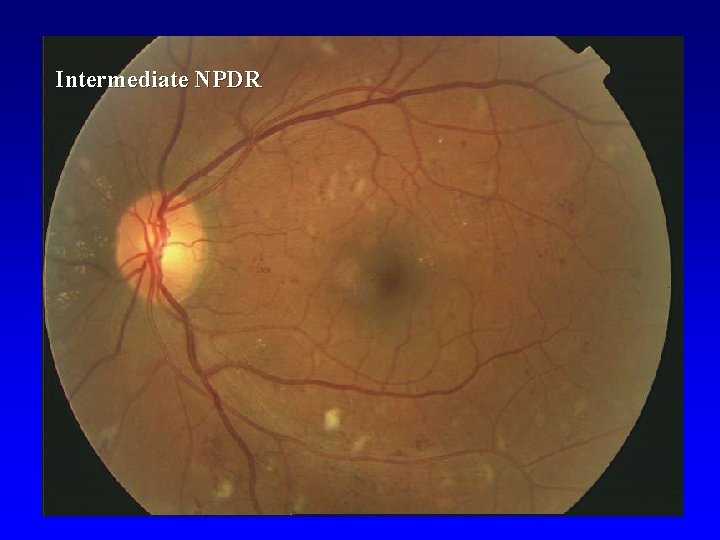

Nonproliferative DR (NPDR) • • • Beginning Intermediate Advanced

Intermediate NPDR

Intermediate NPDR